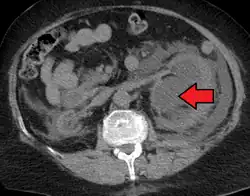

Massive hydronephrosis as marked by the arrow Massive hydronephrosis as marked by the arrow

Stone causing hydronephrosis[16]